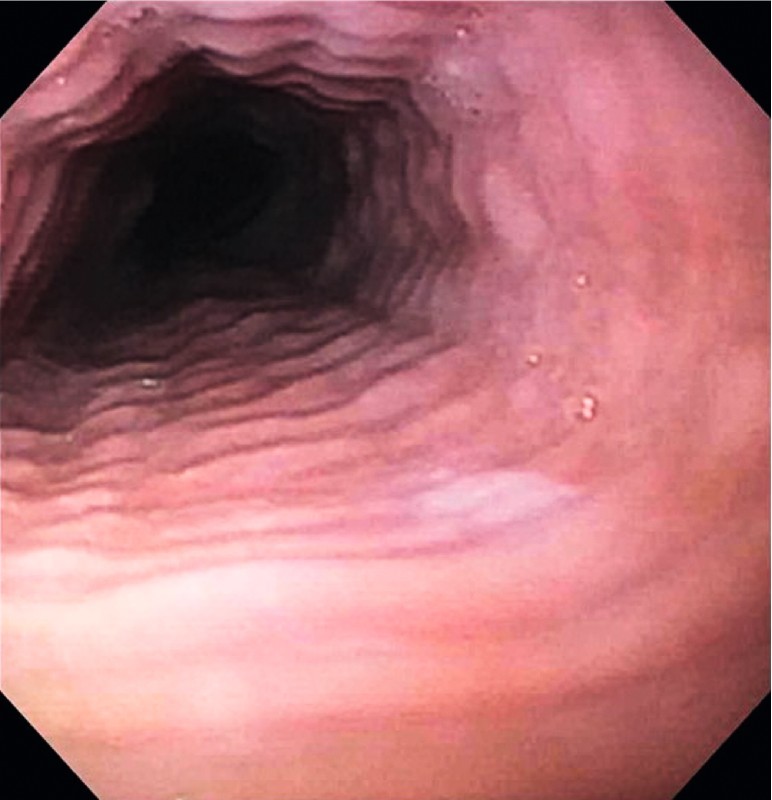

An 81-year-old male presented with 6 months of dysphagia to solid food, episodes of regurgitation, and 18-lb weight loss. Medical and surgical history was significant for bladder cancer status post-bladder resection and ileal conduit. Medications included rabeprazole and multivitamins. There were no environmental or drug allergies. The patient quit smoking 30 years prior, with a 15-pack-year history. He reported daily alcohol intake (1 – 2 drinks/day). The patient underwent an upper endoscopy, which showed esophageal concentric rings ( Fig. 1 ), a proximal web, pseudodiverticula and a distal Schatzki’s ring. Histology showed squamous epithelium with reactive changes infiltrated by 70 lymphocytes per high power field (400-fold magnification), particularly in the peripapillary regions. No intraepithelial eosinophils, neutrophils, or other granulocytes were identified ( Fig. 2 ). Gastric and duodenal biopsies were without lymphocytic involvement. Endoscopy 1 year later demonstrated the same endoscopic and histologic findings. The patient required endoscopic dilation of the esophageal web during both endoscopies and was started on oral fluticasone 220 micrograms twice daily with improvement of symptoms including resolution of his symptoms of dysphagia to solid foods and no further episodes of regurgitation over the subsequent 6-month follow-up.

Fig. 1.

Endoscopy from a patient with lymphocytic esophagitis showing a narrowed esophagus with rings.